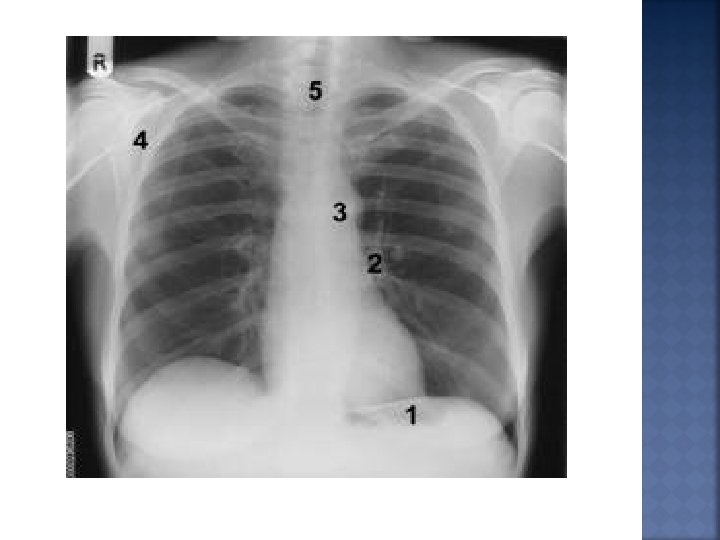

DISORDERS OF THE RESPIRATORY SYSTEM

- Slides: 39